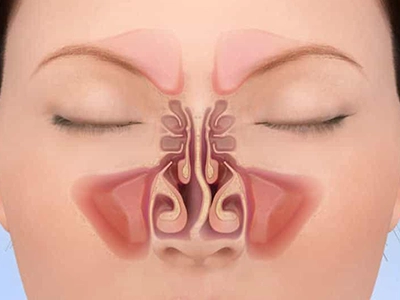

در صورت نیاز، کاهش حجم شاخکهای بینی برای عبور بهتر هوا

جراحی زیبایی بینی (رینوپلاستی) تنها با هدف تغییر ظاهر انجام نمیشود؛ یکی از ارکان مهم موفقیت آن، حفظ یا بهبود عملکرد تنفسی است. پیش از عمل، ارزیابی دقیق مسیرهای تنفسی توسط جراح انجام میشود تا هرگونه انسداد، انحراف تیغه یا تنگی دریچههای بینی مشخص شود.

بررسی داخل بینی با آندوسکوپی برای مشاهده دقیق دریچهها و شاخکهای بینی